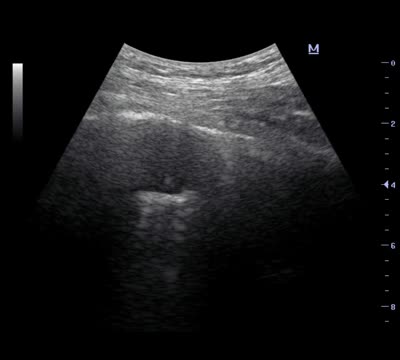

The second case was a 39-year-old female who presented with fever and unresolved pneumonia which had resisted antibiotic therapy for a period of two months. The patient had no history of smoking and her physical examination revealed only bilateral basal fine crepitations. Thoracic CT showed bilateral basal consolidation opacities with positive air bronchogram. Microbiological examination for sputum and bronchoalveolar lavage samples were negative, including the tuberculosis work-up. For the diagnosis of the underlying pathology, the patient was subjected to r-EBUS assisted transbronchial cryobiopsy guided with transthoracic ultrasound. During the procedure, the radial probe was advanced through the lateral segment of the left lower lobe until the lesion was visible. Then, the 1.9mm flexible cryoprobe was advanced to the target location. Simultaneously, the transthoracic ultrasound was applied on the chest wall and was able to detect the lesion. The transthoracic ultrasound was helpful in confirming that the cryoprobe was located within the lesion and distant from the pleura to avoid pneumothorax. Four transbronchial cryobiopsies were obtained and the histopathological examination revealed cryptogenic organizing pneumonia.